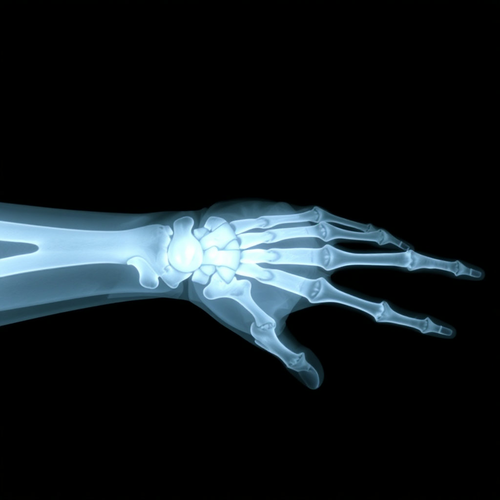

엑스레이(X-ray)는 우리 눈에는 보이지 않는 특별한 빛이에요. 이 빛은 아주 짧은 파장을 가지고 있어서 높은 에너지를 가지고 있어요. 이 엑스레이 빛은 1895년에 독일의 과학자 뢴트겐이 우연히 발견했답니다.

엑스레이는 살과 근육과 같은 부드러운 조직은 쉽게 통과하지만, 뼈처럼 단단하고 밀도가 높은 물질은 통과하지 못해요. 그래서 엑스레이를 사용하면 몸속의 뼈를 하얗게, 그리고 살과 근육, 피와 피부 같은 부드러운 조직은 엑스레이가 잘 통과해서 검거나 회색으로 보이게 만들 수 있어요.

엑스레이가 이미지를 만드는 과정은 엑스레이 장비에 신체를 밀착하고 찍으면, 기계에서 엑스레이 빛이 나와 몸을 통과해요. 이 빛은 몸속을 지나면서 각 조직의 밀도에 따라 다르게 흡수됩니다. 뼈나 금속 같은 딱딱한 물질은 엑스레이를 많이 흡수해서 하얗게 보이고, 살과 근육과 같은 밀도가 낮은 부분은 엑스레이를 거의 흡수하지 않아 검게 보이죠. 이렇게 흡수된 엑스레이는 감지기에 도달해 이미지를 만들어냅니다. 이 이미지를 통해 의사 선생님은 몸속의 상태를 확인할 수 있어요.